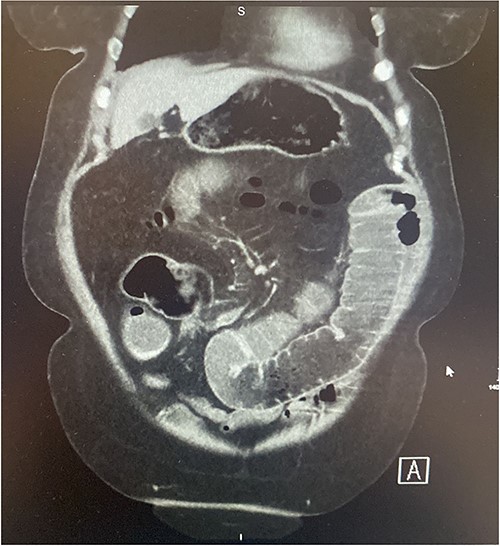

A 73-year-old female presented complaining of acute onset right sided upper abdominal pain associated with three episodes of bilious vomitus and constipation. Clinically, her abdomen was tender, distended, and tympanic with increased bowel sounds. Of note, she described a 3-month history of repeated low grade abdominal pain with vomiting. The clinical picture was concerning for that of bowel obstruction. Contrast enhanced CT scan of the abdomen and pelvis (CTAP) demonstrated multiple dilated loops of small bowel measuring 4.5 cm at their maximum calibre. In the right abdomen there was a focus of ileo-ileal intussusception with a filling defect measuring ~6–7 cm (Figs 1–2). Multiple enlarged enhancing lymph nodes, measuring up to 10 mm, were identified at the level of the intussusception. The duodenum, distal ileum, and jejunum were collapsed.

Axial section of contrast enhanced CT AP demonstrating intussusception with surrounding lymphadenopathy.